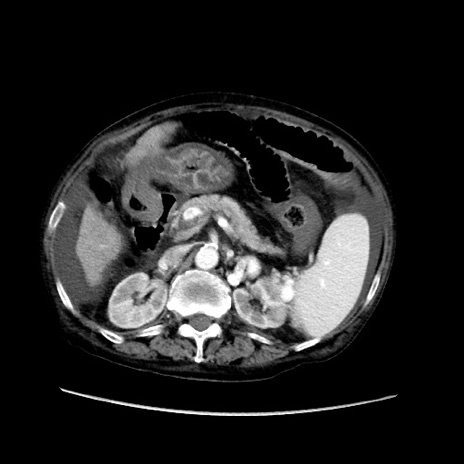

矢状断像